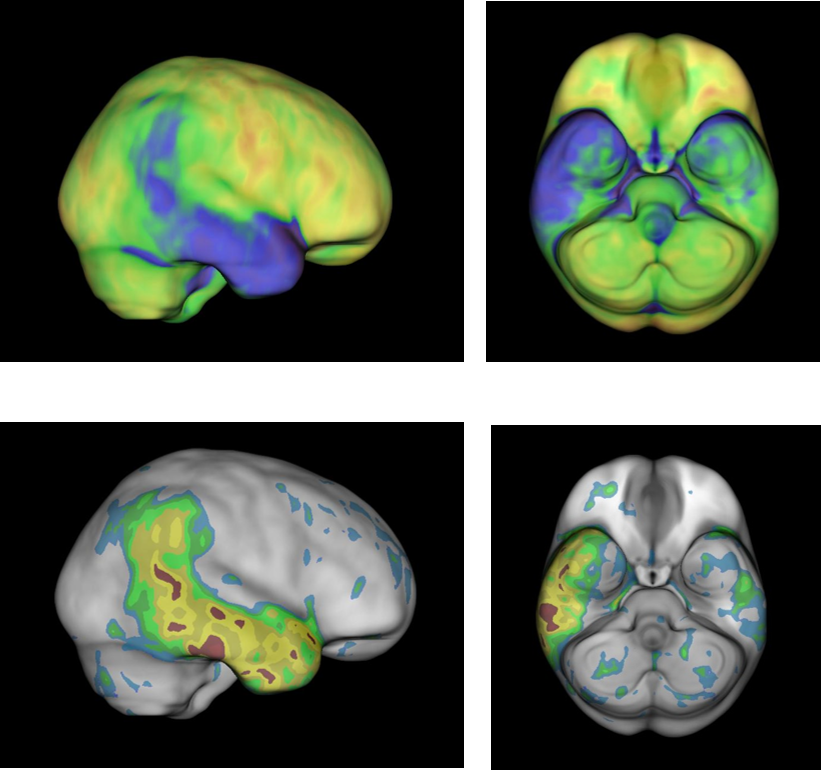

“Le immagini sono paragonabili a quelle delle PET – prosegue Aricò – ma con alcune differenze in quanto la SPECT/TC è eseguita solo in caso di necessità (come approfondimento richiesto dal Medico Nucleare) e solo sul distretto interessato come il torace, l’addome, il cervello, ecc., ottimizzando le tempistiche e il comfort del paziente. La SPECT/TC è molto utile in diverse applicazioni cliniche e coinvolge trasversalmente molte discipline mediche come la cardiologia, l’ortopedia, l’endocrinochirurgia, le malattie infettive ed anche la neurologia.“

Grazie alla continua evoluzione delle tecnologie, l’accuratezza e l’affidabilità delle immagini prodotte dalla gamma camera sono in costante miglioramento, aprendo la strada a nuove scoperte e nuove applicazioni in campo medico. Tra le applicazioni di maggiore rilievo quella relativa alla chirurgia radioguidata per la ricerca del linfonodo sentinella nel tumore della mammella e nei melanomi. La qualità delle immagini permette infatti di individuare con precisione anatomica l’area in cui è necessario intervenire.